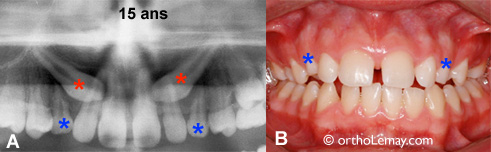

15 ans

(A, B) Il est déjà trop tard pour ce patient de 15 ans chez qui les canines permanentes (* rouges) si dirigent vers le centre du côté du palais. Les canines temporaires auraient dû être extraites il y a plusieurs années pour donner une meilleure chance d’éruption normale aux canines.